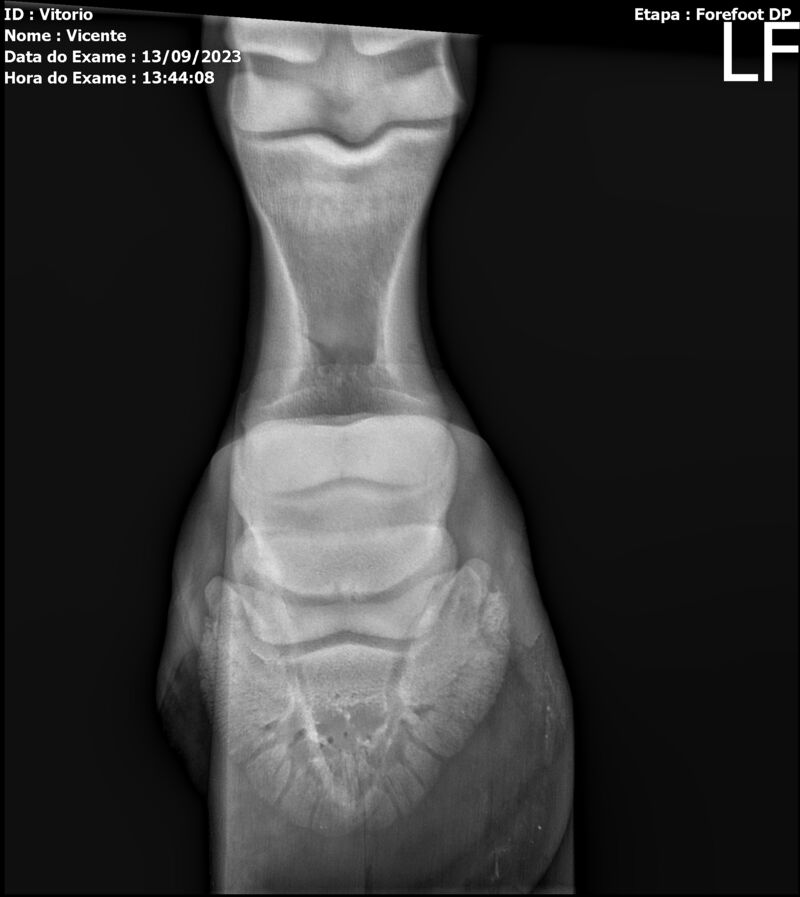

LOTE 13

THUNDER ZC

Raça: BRASILEIRO DE HIPISMO

Sexo: MACHO - POTRO

Nascimento: 17/09/2022

Altura Aproximada: 1,54

Pel.: CASTANHO

Registro: EM AND

Vend.: VICENTE CONTE

Local : PORTO FELIZ/SP